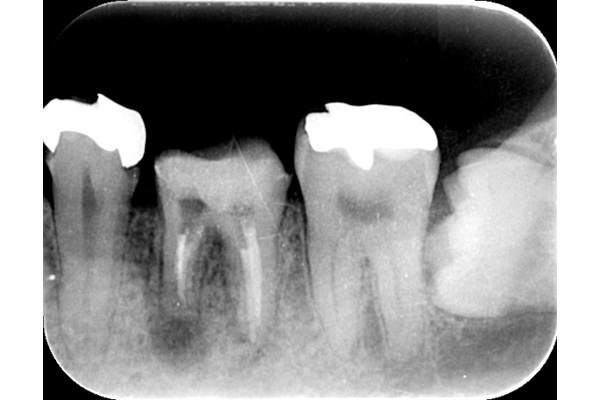

根の先端に膿が溜まっています。

根の中の白い縦の線がなくなっています。これは、中に詰まっていた、防腐剤を取り除いた証拠になります。取り除いてから、根の中をしっかり清掃していきます。

清掃が終わり、患者様も違和感がなくなったということで、防腐剤を再び詰めていきました。最初に入っていたものと比較して緊密に太く入っているのがわかります。

6ヶ月後。根の先端に溜まっていた膿(黒い影)がなくなっています。なくなったことが確認できてから、かぶせ物をかぶせていきます。